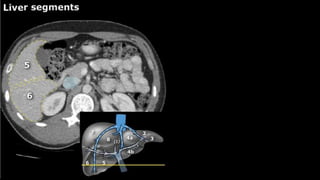

•Liver • A normalliver enhances homogeneously (irrespective of the scan phase). The liver receives about 80% of its blood through the portal vein (= nutrient-rich blood from the intestines). The remaining 20% is supplied by the hepatic artery. y is present, it is important to document its location. This may be crucial to any surgical options. Using the Couinaud classification, the liver is subdivided into eight individually functioning segments. Each segment has its own afferent hepatic artery and portal vein, and efferent hepatic vein and efferent bile ducts